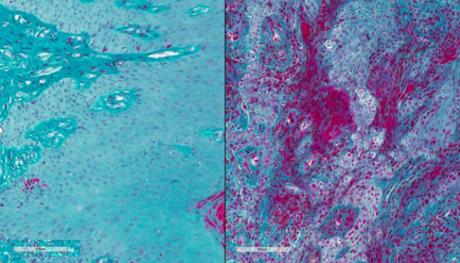

La parodontite est une infection bactérienne des tissus soutenant les dents. À ses débuts, la maladie parodontale provoque une rougeur et un gonflement (inflammation) des gencives (visuel de droite). Dans les stades plus avancés, l'os sous-jacent est endommagé, ce qui entraîne la perte des dents. La parodontite est due en partie à une réponse cellulaire immunitaire exagérée mais ses mécanismes moléculaires sous-jacents ne sont pas bien compris. « Une maladie parodontale grave peut entraîner la perte des dents et réduire considérablement la qualité de vie de nombreuses personnes, en particulier plus âgées ou qui n’ont pas accès aux soins dentaires », explique le Dr Rena D'Souza, Directrice du NIDCR.